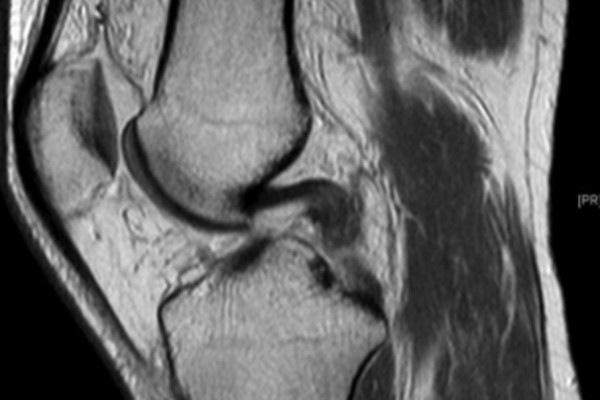

Ist das Kreuzband vollständig abgerissen ist eine Heilung ohne Operation nicht möglich. Um das Kreuzband dennoch zu erhalten kommt die Ligamys® Technik oder „Dynamische Intraligamentäre Stabilisierung“ zum Einsatz. Hierbei wird das abgerissene Kreuzband über eine wenig Millimeter messende Bohrung mit Nähten wieder am Oberschenkelknochen fixiert. Um die Naht in der Zeit der Heilung zu schützen wird eine stabile Kordel als innere Schienung parallel zum Kreuzband gespannt. Diese Kordel wird im Unterschenkelknochen im eigentlichen Ligamys® Implantat verankert. Hier sorgt eine Feder dafür, dass die Kordel über das gesamte Bewegungsausmaß die selbe Spannung behält. Der gesamte Eingriff wird im Rahmen einer Kniegelenksspiegelung also ohne weite Eröffnung des Kniegelenks durchgeführt.